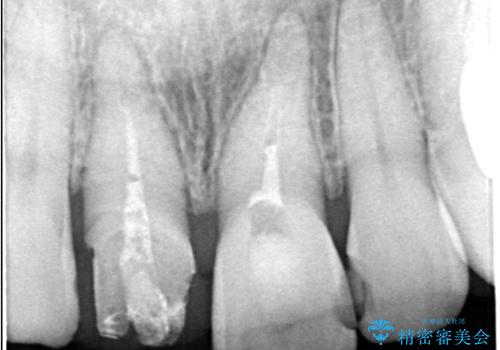

- 気を失って転倒し、前歯をぶつけたことをきっかけに「かかりつけ医で抜歯と診断された」との主訴で来院された患者様です。

レントゲン撮影や顕微鏡下での精査、メチレンブルーによる染色検査を行った結果、破折線は認められず、保存可能と判断しました。

精密根管治療を行い、その後オールセラミッククラウンで審美的に修復しています。あわせてホワイトニングとエアフローによるクリーニングも行い、自然で美しい仕上がりとなりました。